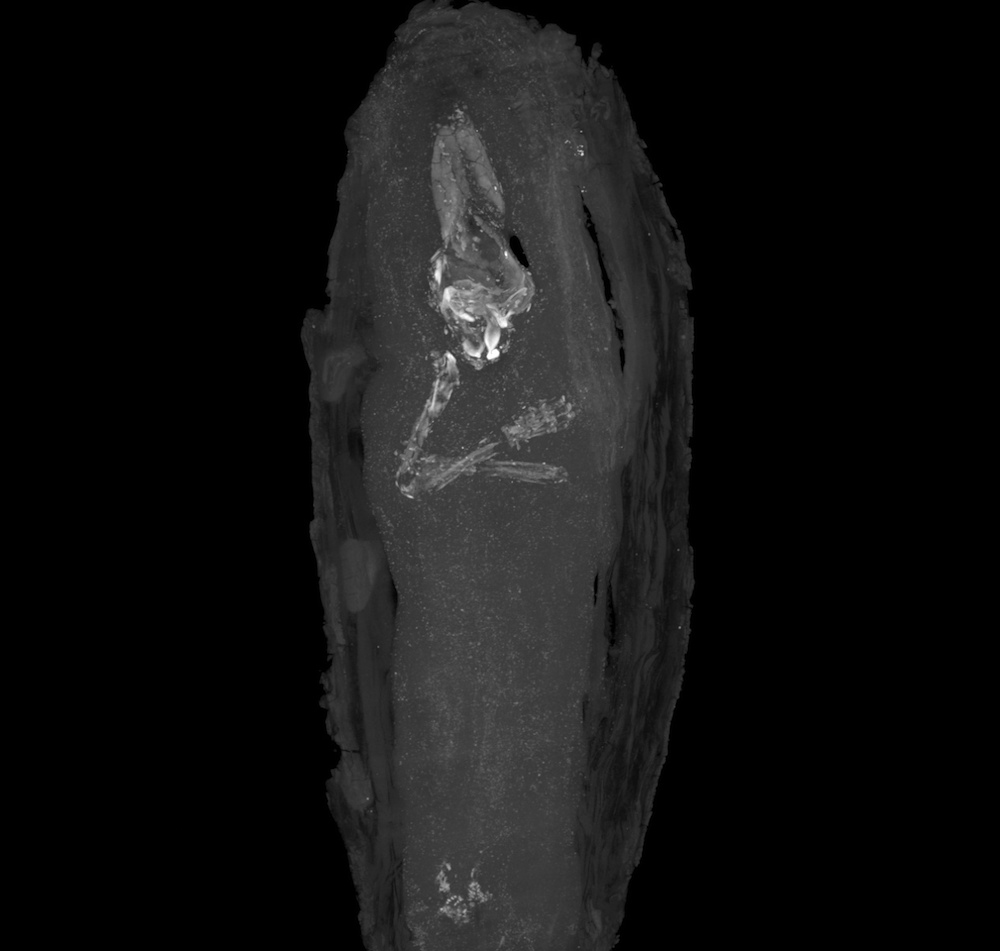

A miniature coffin in the Fitzwilliam Museum in Cambridge, England, holds what appears to be the youngest known Egyptian mummy. The coffin, made of cedar wood, was discovered at Giza in 1907 and dates back more than 2,500 years.

The fetus inside the coffin was only 16-18 weeks old after the time of gestation (when it was conceived) and likely died from a miscarriage. The coffin, which has tiny carvings on it, had been in the museum for over a century, but curators had assumed that it probably held internal organs from someone who was mummified. Not until CT scans were performed was the occupant of the tiny coffin revealed.